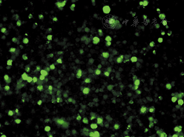

通过荧光倒置显微镜观察转染后细胞形态变化,转染后24 h的部分K562细胞发出绿色荧光信号,部分细胞膨胀,细胞壁有皱褶或破损,形态完整(图1)。转染率为(53.4±3.2)%。